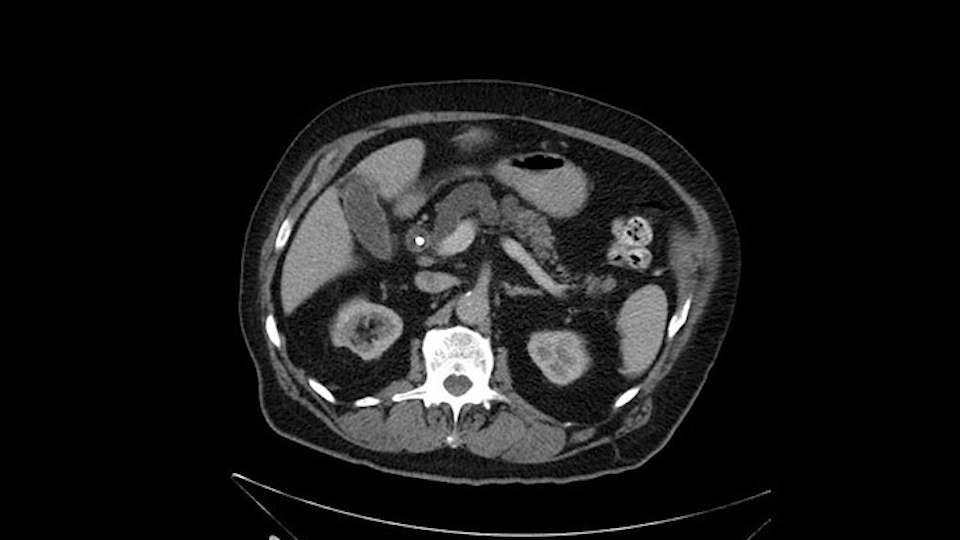

Anyhow. What the surgeon does need to do though, is focus on the resection. What I generally do is look at the tumor, which is here, and then I look at the nature of the pancreas. That’s really just to get an idea on what it would be like to do the pancreatic anastomosis, which isn’t technically the biggest deal, but it’s the biggest deal for the patient afterwards; and the larger the duct and the harder the pancreas, the less likely it’s going to leak. Leaks are what cause almost all the morbidity so I do think of it mentally. I wouldn’t do anything differently, the night before or the morning or the surgery or during the surgery, but certainly mentally it’s useful to know that you may have a challenge in terms of doing the best pancreatic anastomosis you can. I think the duct is quite large. The interesting thing about the duct: it does peter out into fairly normal looking pancreas; that’s a bit strange. But I’ll assume the duct is large.

The next item that I would look at: the issue would be the vessels and usually start at the portal vein, watch the portal vein, follow it down, down-down-down to the neck of the pancreas - which is here - and there’s no impingement by tumor, which is great. The SMV and the splenic vein, which is here. The splenic vein junction is normal, which is great.

Then look at the first jejunal branch - which is this thing here - this little branch which goes under the SMA. It’s something that we’ve just started appreciating over the past few years and the reason for that is: there’s two or three small branches that come out of the uncinate into the the first jejunal and it’s a fairly inevitable part of the operation where there’s some bleeding. As long as you’re cognizant of what’s happening, it’s no reason to panic and that kind of bleeding will eventually stop or can be stopped but it’s not easy because these little vessels are fragile from the uncinate to the first jejunal. So I do focus on that and it’s pretty consistent I’d say 9 times out of 10, people have that first jejunal.

The other thing I look at is the gastroepeiploic arcade- which is this thing here- which is where the gastroepeiploic vein joins the portal vein. I call it the gateway to the neck of the pancreas because you pretty much have to divide it to get to the neck. The middle colic vein usually drains either into it or nearby. I think we’re seeing it here. Again,that can be divided and I usually divide those two and it helps me get under the neck. Again, there’s no issues here with the tumor so it’s nice from that perspective. If I was concerned about the vein, which I’m not here, I would go to the coronal view. It’s a nice way to look at the vein on just a couple of cuts and you can see a beautiful view of it here. There’s the portal vein, there’s the head of the pancreas. There’s the tumor. It’s a little closer here than it looks on the other one. I doubt it’s involved. If it’s touching, it may not be invading it but even if it was, it's a short segment. Anyways, there’s the SMV there’s the splenic vein, and everything looks good. You can see the stent. I ignore the stent. It’s the most dramatic looking thing in the picture but it’s actually the least important.

Then either through the coronal or the axial, I’ll do both. Look at the SMA -which is here- I had already looked at it and I don’t see any involvement. There’s the SMA with a nice fat plane between the SMA and the tumor. Over here you can see on the axial, there’s the SMA. Everything on the right side of the SMA has got some nice black around it, which is fat, which means probably no tumor [no tumor, no tumor]. Follow it up to the origin, coming off the aorta. So those are the two technical things that I worry about: the SMA and the SMV.